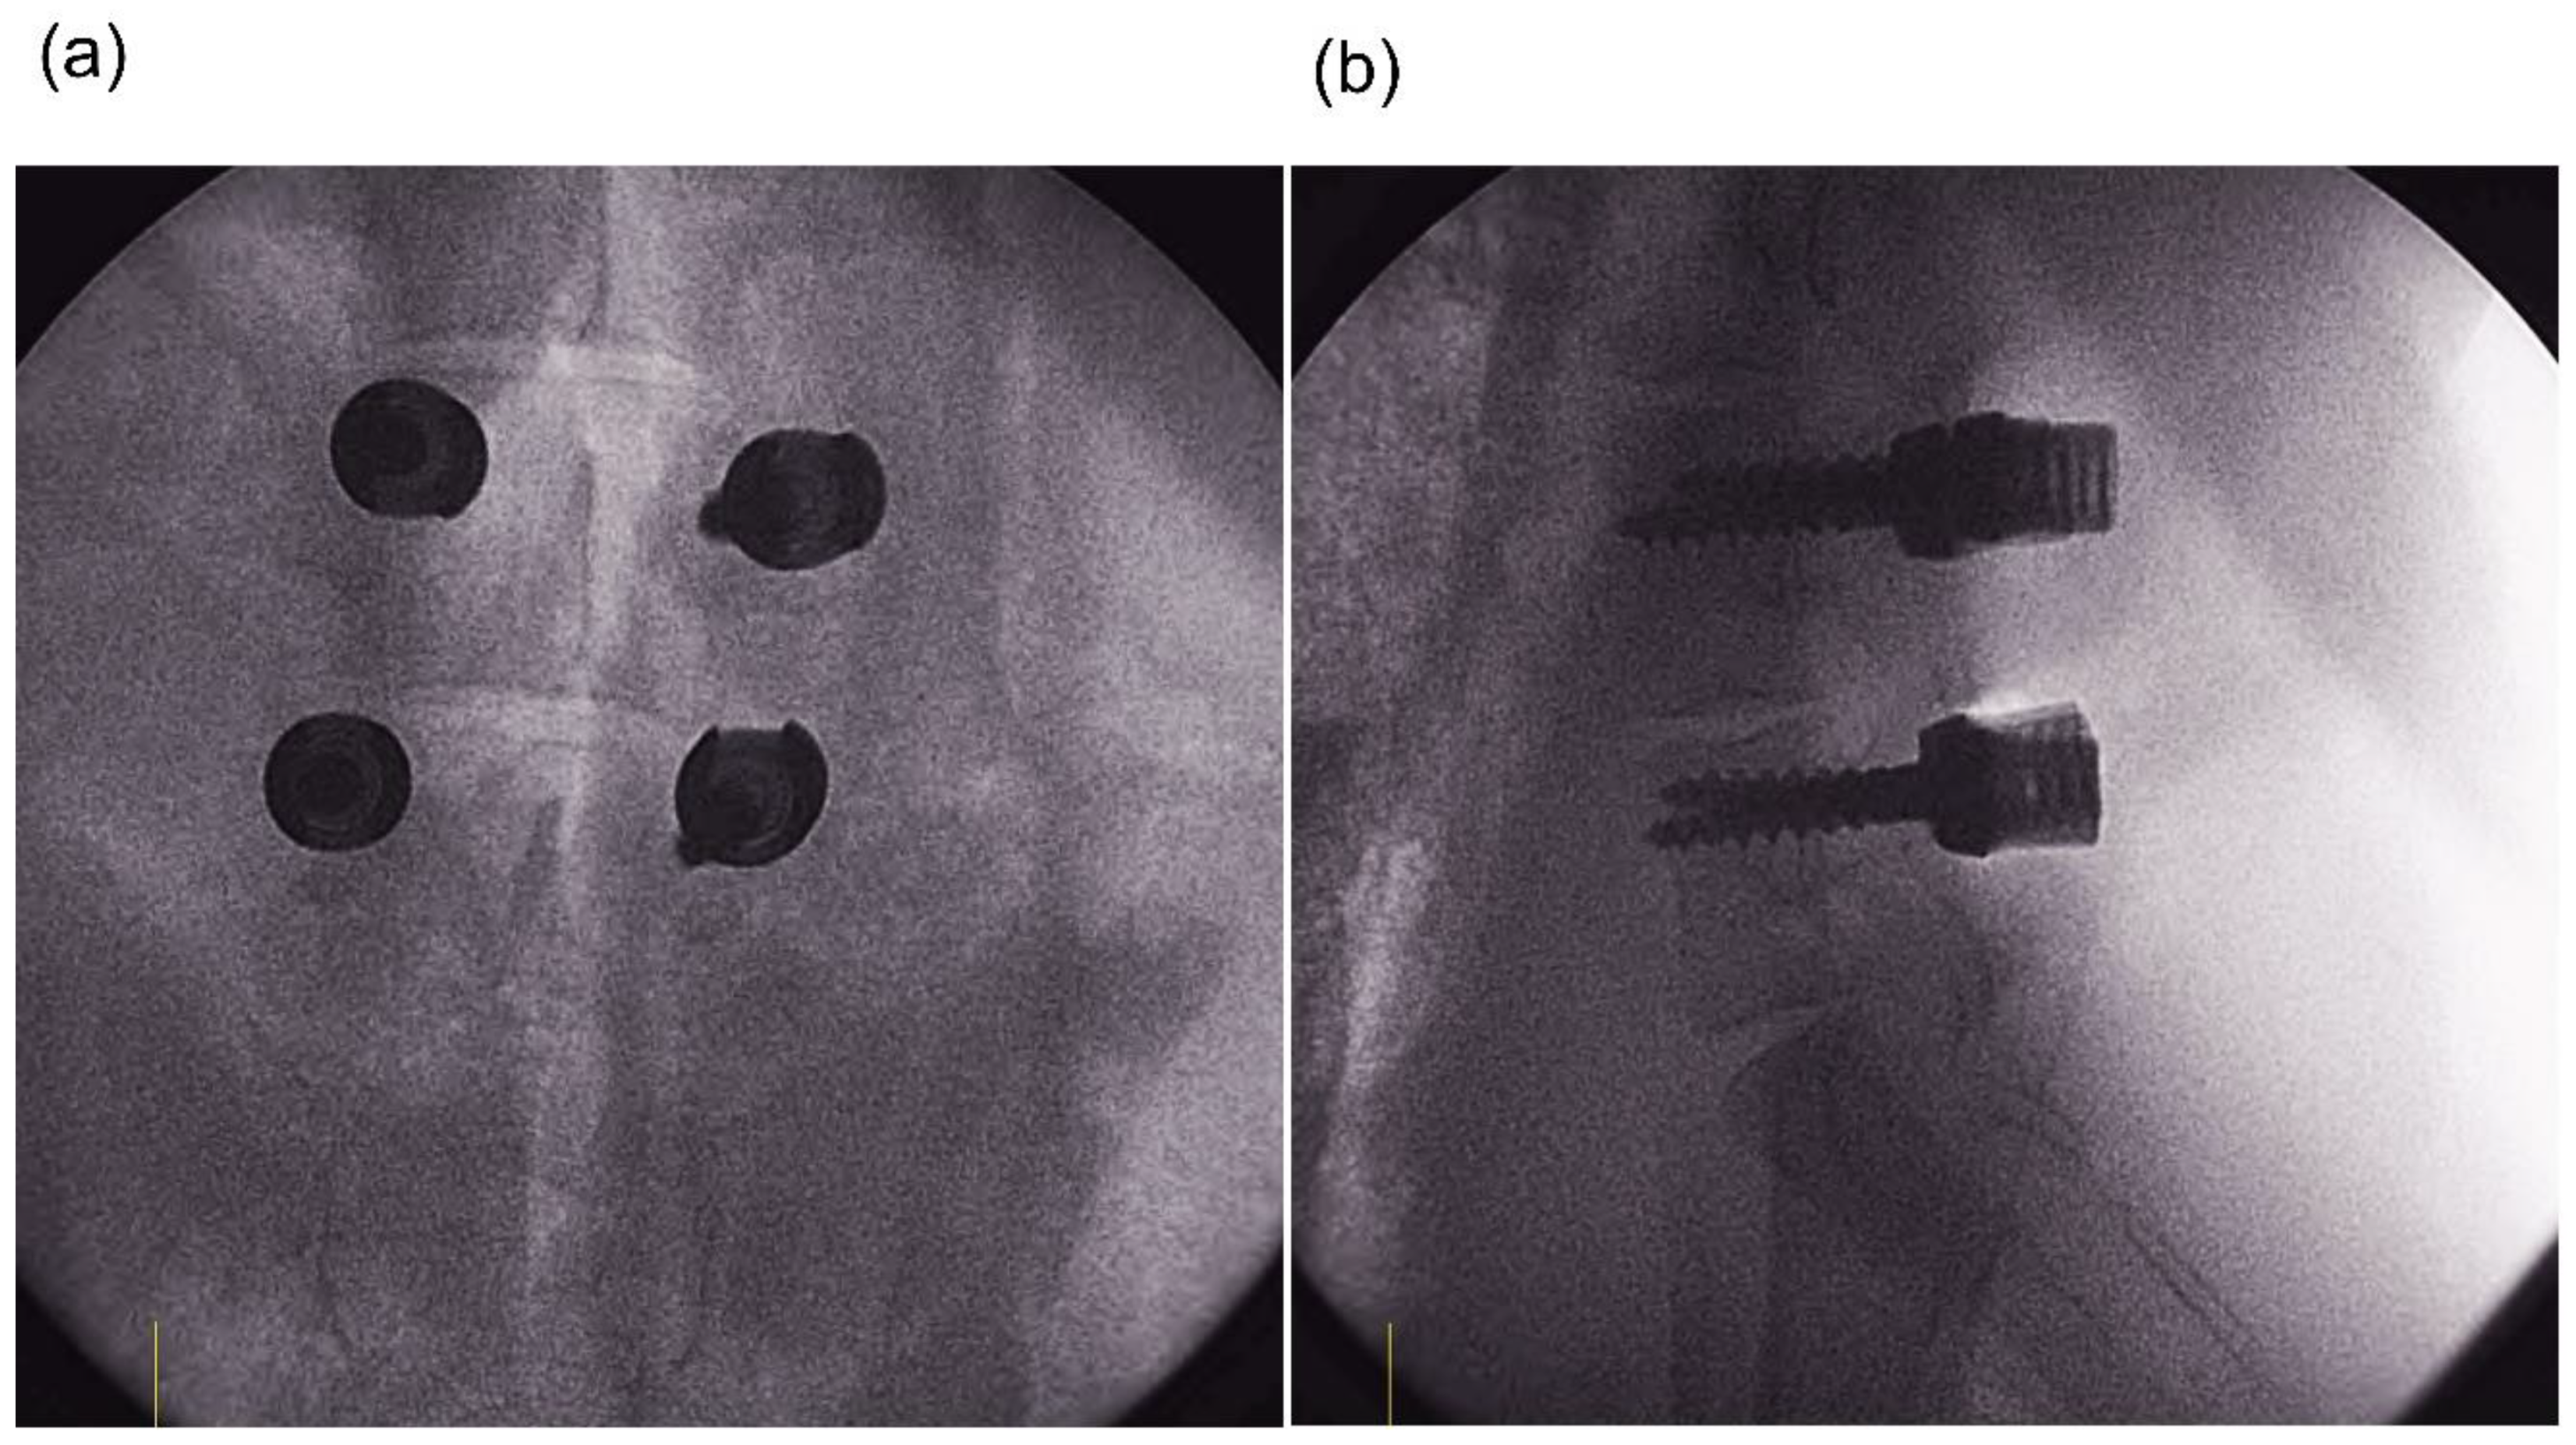

2. Materials and Methods

2.1. Animal Experiment